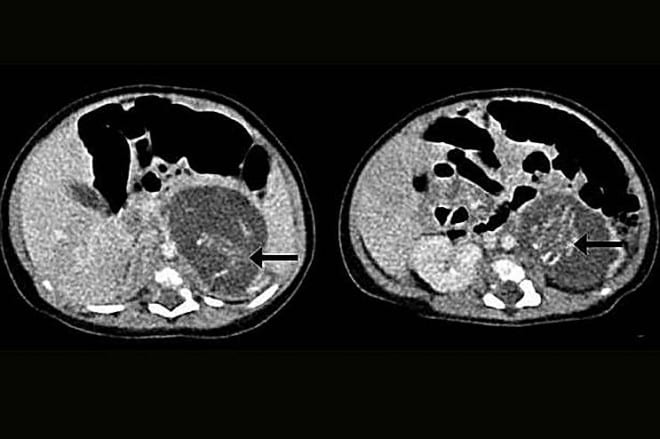

Une petite fille née à Hong Kong a été jugée «enceinte» de jumeaux.

La petite fille, née de parents venant de la Chine continentale à l’hôpital Queen Elizabeth a dû subir une intervention chirurgicale à seulement âgée de trois semaines pour les enlever.

Les fœtus, 8 à 10 semaines en gestation, avaient des jambes, des bras, une colonne vertébrale, de la cage thoracique et des intestins.

Un pesait 14,2 grammes et l’autre 9,3 grammes – et chacun avait un cordon ombilical.

La condition, connue sous le nom de fœtus dans foetu se produit dans seulement un sur 500 000 naissances dans le monde. Moins 200 cas ont déjà été signalés.